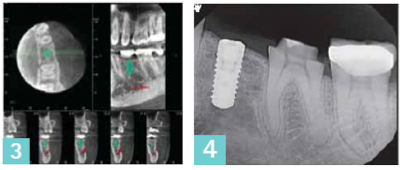

The case presented represents a typical instance where an implant is required in the area of the first or second premolar. A three-dimensional scan is used to accurately locate the exact position of important anatomic structures or landmarks. The 3D scan and software allow moving, slicing, and viewing the anatomy from any direction.

A critical step is the ability to mark the position of the nerve (marked in red in the images below) — this becomes especially helpful when virtual implants are used. A first look might indicate that the implant on this image (1) could interfere with the inferior alveolar nerve and mental foramen. This is not the case. This image (2) is a disto-facial view of the 3D scan showing appropriate clearance between the implant, inferior nerve, and the mental foramen — as indicated by the mint circle. In addition, the Invivo5 software provides a visual indication of such clearance by coloring green the implant model in the lower left of the screen. |